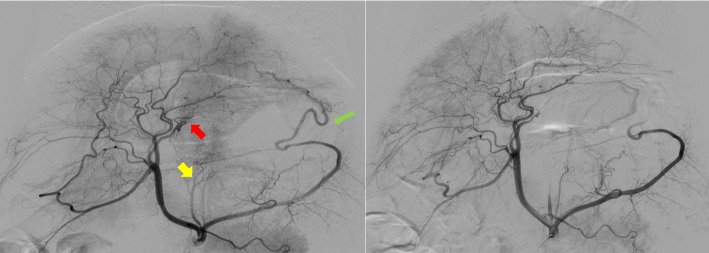

Materials and methods: Fifteen healthy juvenile male farm pigs were randomly allocated into three groups: NBCA embolization (n = 5), microsphere embolization (n = 5), and a control group (n = 5). Embolization targeted the right, left, and short gastric arteries. Weight and fasting plasma ghrelin levels were monitored weekly for 16 weeks. Gastric endoscopy was performed 1 and 4 weeks post-BAE, and each animal's ghrelin-expressing cells in the stomach's fundus, body, and antrum were analyzed.